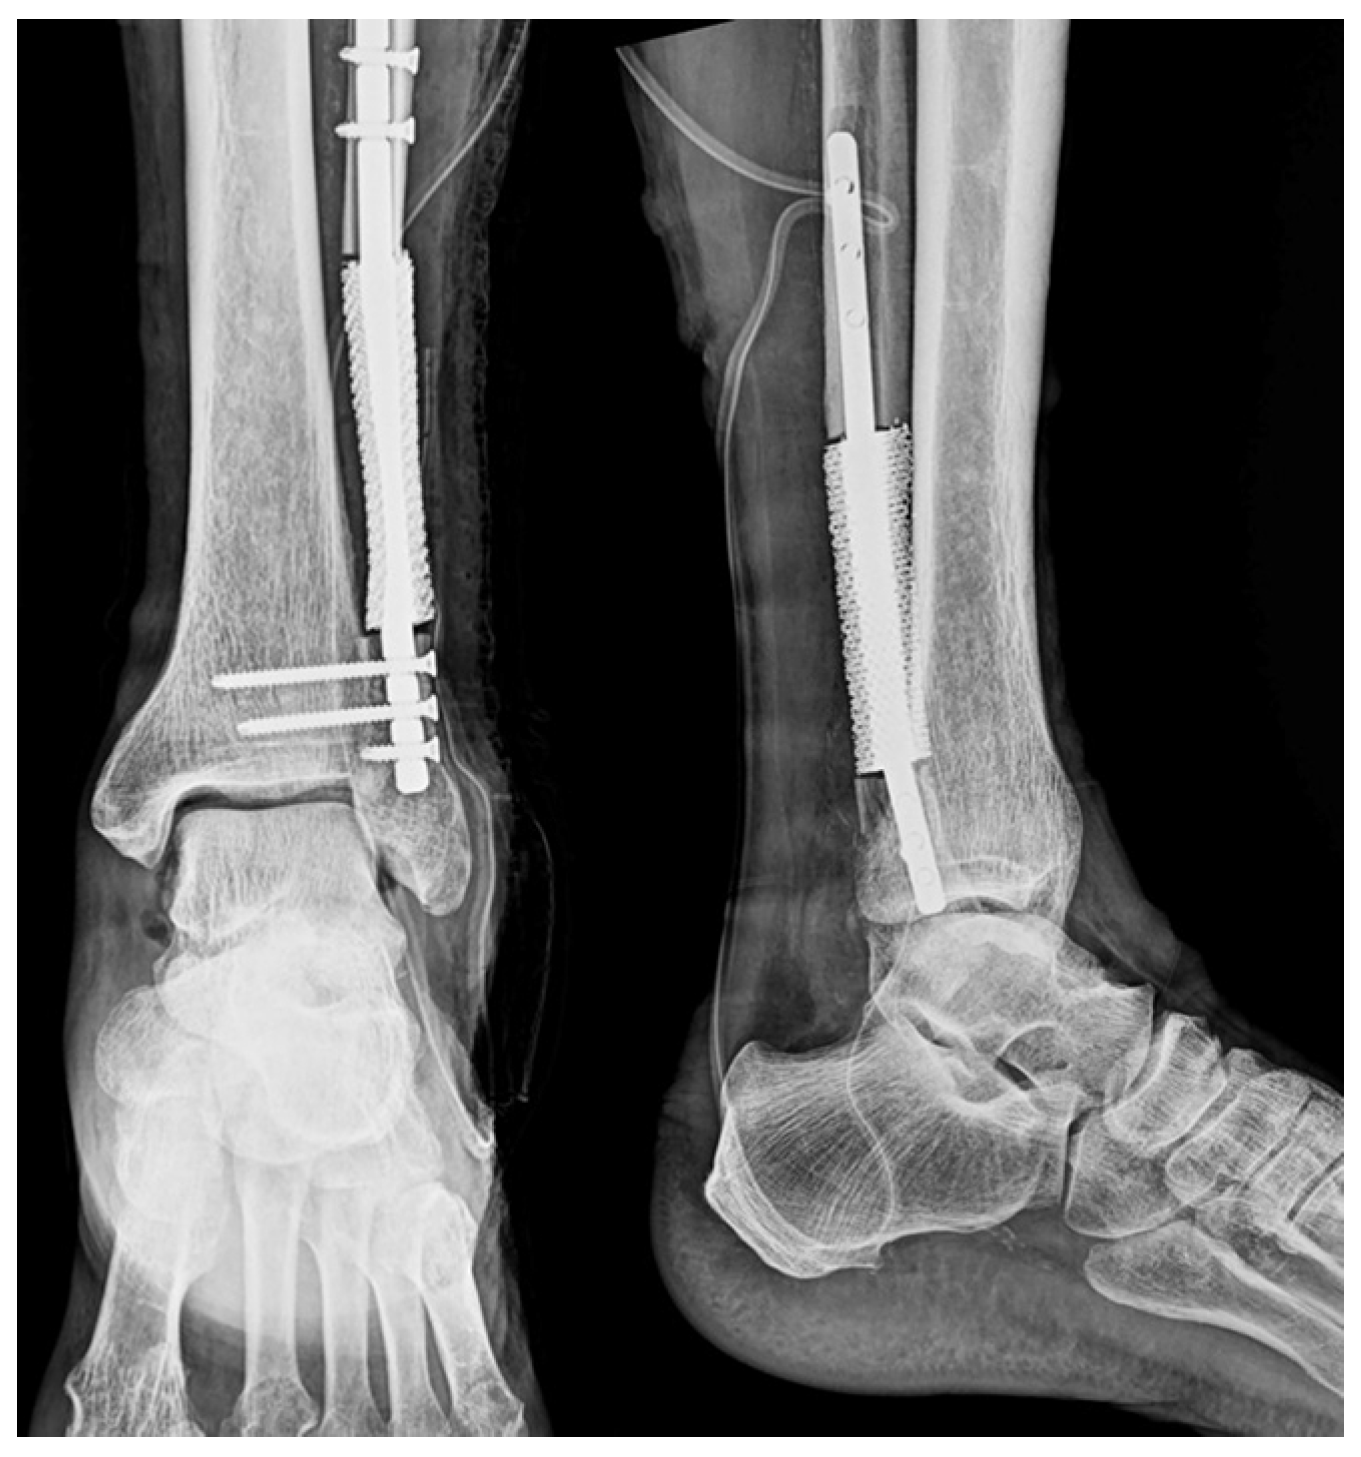

Postoperative radiographs confirmed stable prosthesis placement and proper alignment (Figure 8). The pathological findings were consistent with low-grade chondrosarcoma (Grade I).

Figure 8. Postoperative imaging. Postoperative radiographs of the ankle in anteroposterior and lateral views showing stable fixation with a locking plate with proper prosthesis placement.